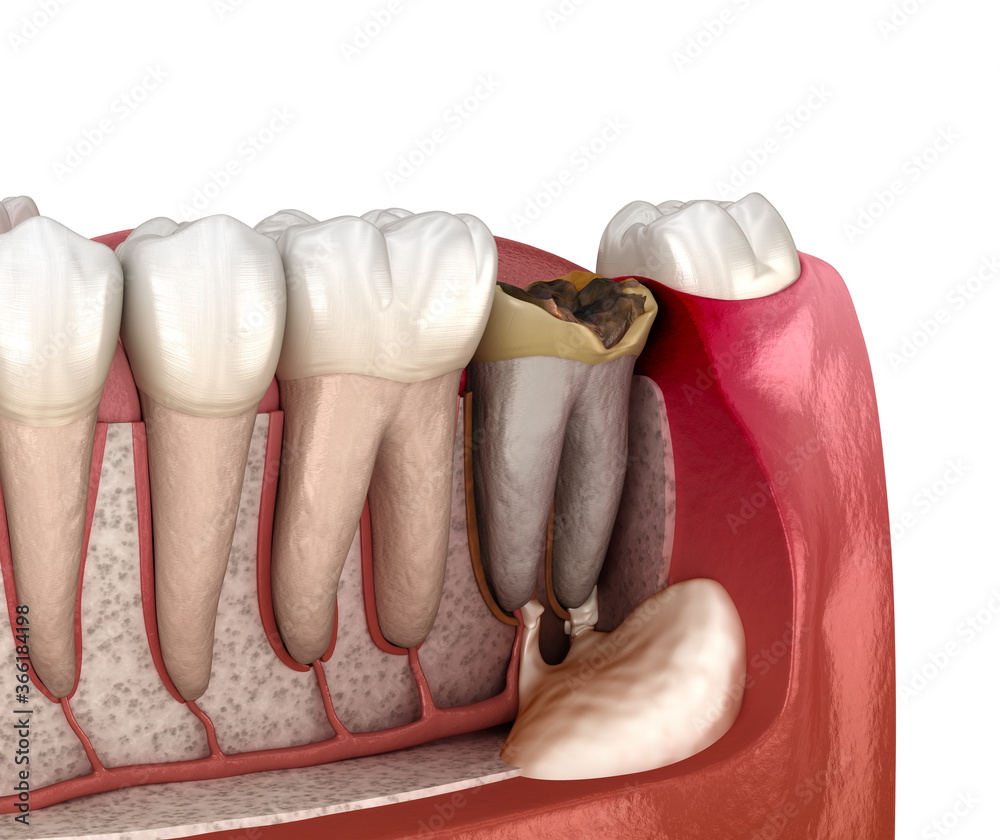

From www.dreamstime.com

Periostitis Tooth Lump on Gum Above Tooth. Medically Accurate Dental Periostitis Jaw What are the histologic and. — chronic osteomyelitis with proliferative periostitis is a rare form of osteomyelitis that is characterised by new. — garre’s osteomyelitis of the jaw refers to a particular type of pathological change and clinical manifestation of chronic marginal. — a total of 156 patients with chronic osteomyelitis, proliferative periostitis (garre osteomyelitis),. this. Periostitis Jaw.